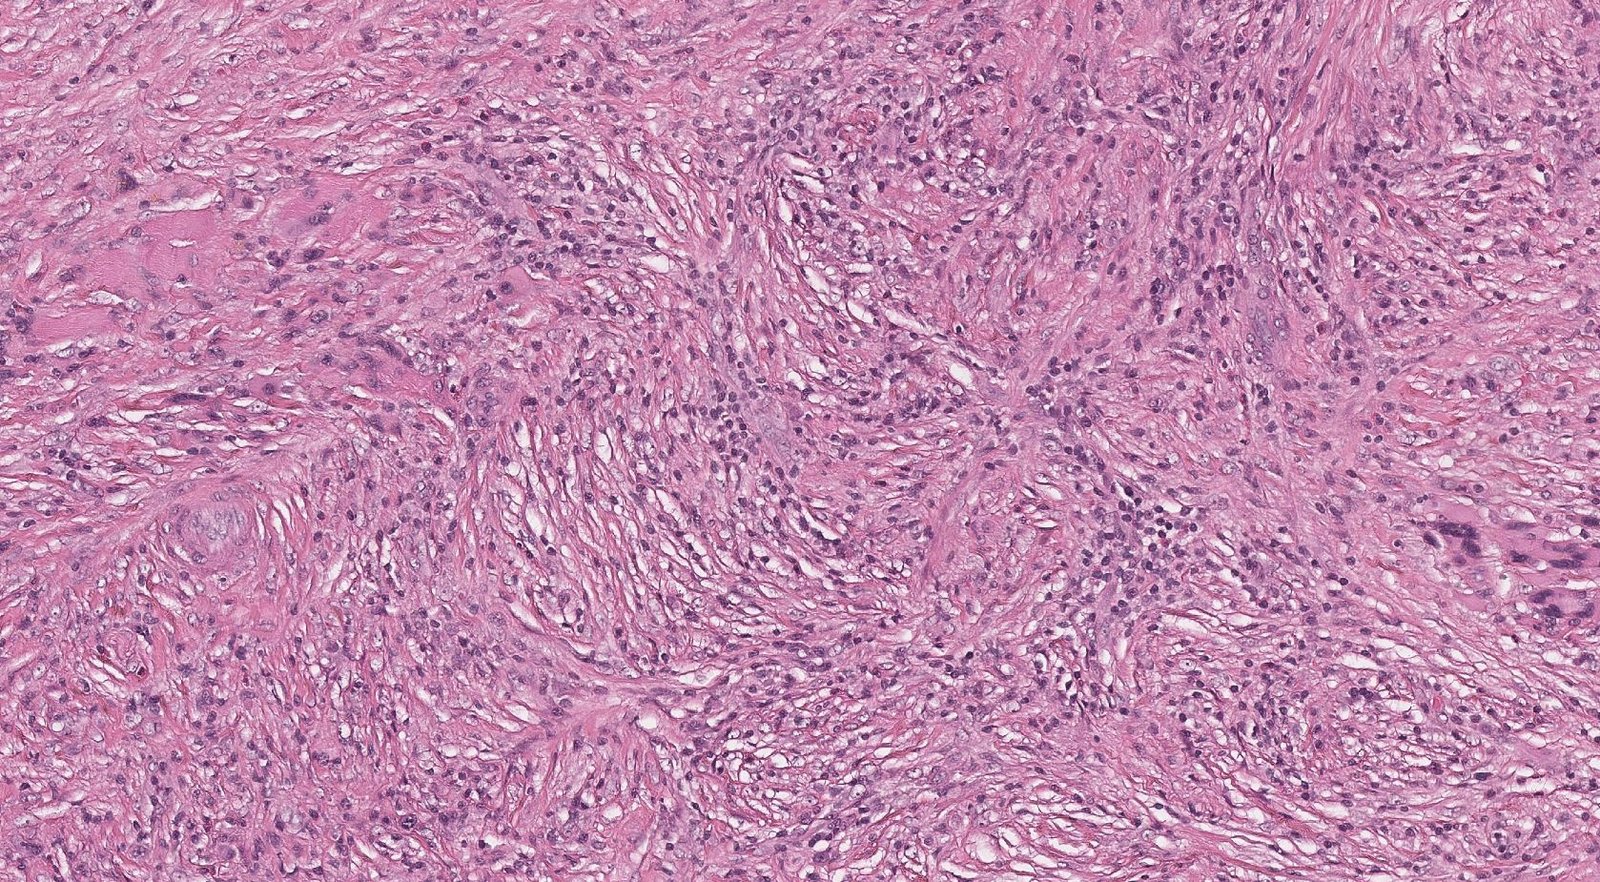

Case: LungMass

Specials to Order:

Final Diagnosis: